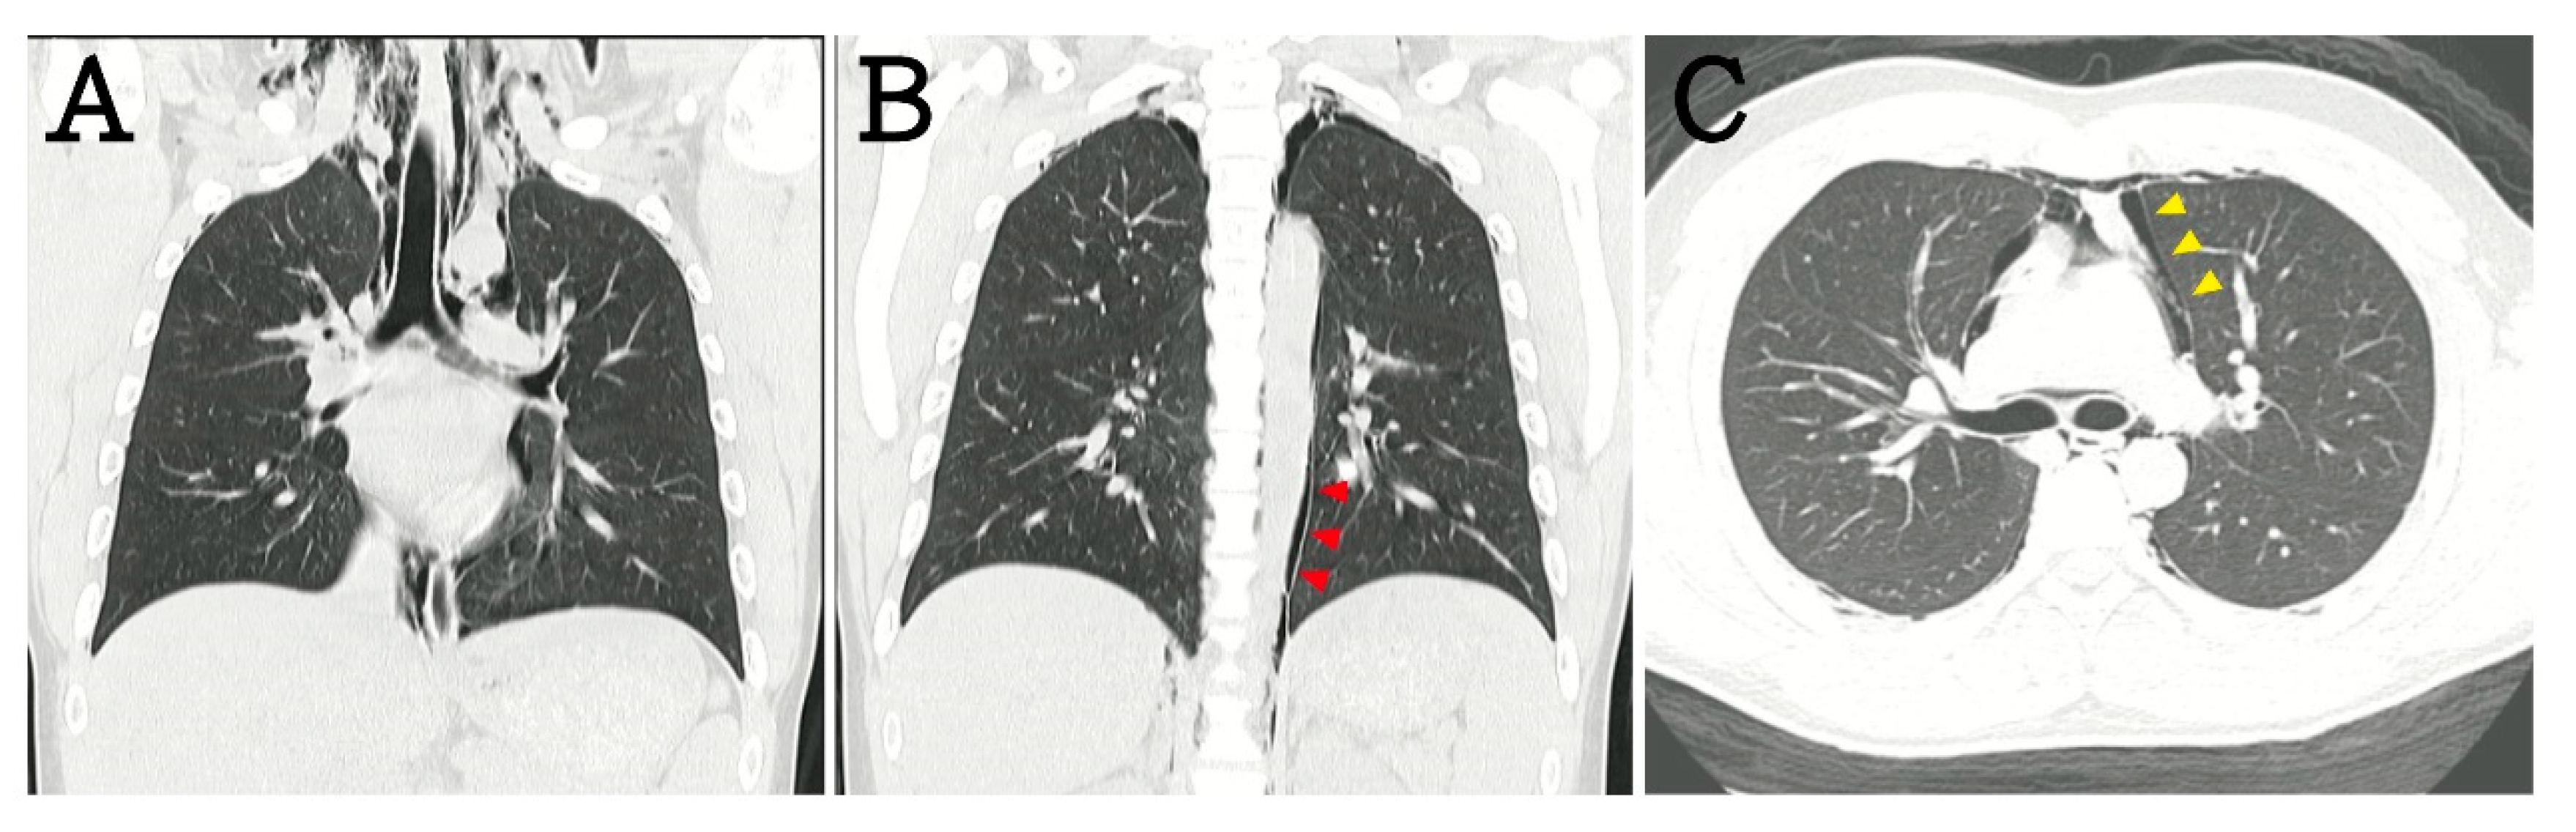

2. Case Presentation